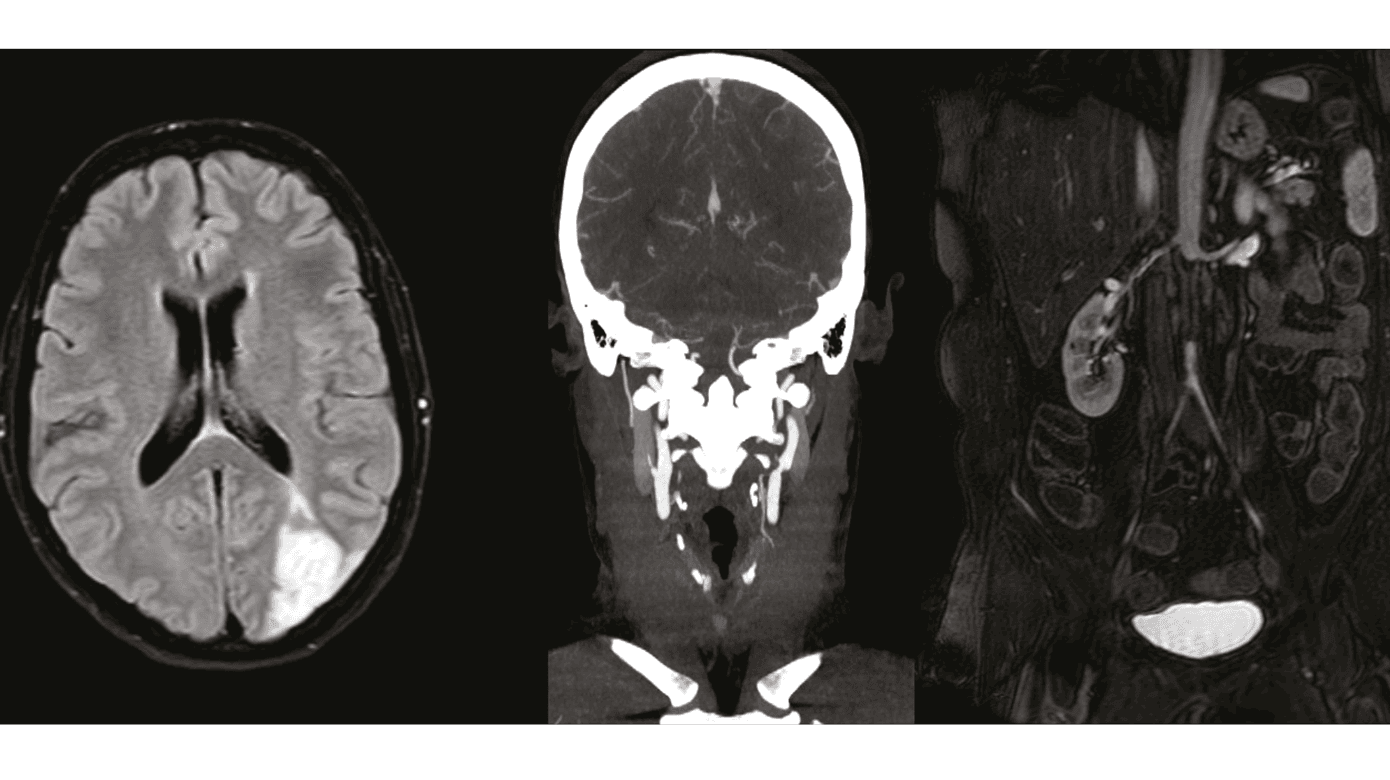

En 44-årig kvinde med Sjögrens syndrom og mangeårig fibromyalgi blev indlagt grundet hovedpine varende tre uger og ordmobiliseringsbesvær varende en uge, ændret finmotorik i højre hånd samt fokuserings- og forståelsesvanskeligheder ved skrivning og læsning. En neurologisk undersøgelse viste herudover højresidig øvre homonym kvadrantanopsi og visuel inattention mod højre. MR-skanning af cerebrum viste subakutte infarkter i venstre vandskelsområder, og CT-angiografi af hjerne og halskar viste svære stenoser proksimalt i venstre a. carotis interna, a. carotis externa og a. subclavia (Figur 1 A + B).

Patienten klagede over smerter i venstre arm med forværring ved brug og havde gennem syv år haft tiltagende smerter i begge ben med forværring ved gang. Ved indlæggelsen kunne hun gå 50 meter med rollator, men var primært mobiliseret i kørestol. Det seneste år oplevede hun ved gang tab af følesans fra navlen og nedefter samt tab af kontrol over defækation og vandladning. CT-og MR-angiografi viste okklusion af aorta abdominalis infrarenalt med genåbning ved bifurkaturen og spinkle aa. iliacae (Figur 1C). MR-skanning af medulla spinalis var normal. Ved karkirurgisk vurdering fandt man manglende lyske- og fodpuls i begge ben, ankeltryk på 30-40 mmHg (normalt 10-20 mmHg højere end højeste armtryk), manglende håndledpuls venstresidigt samt blodtryk på 106/64 mmHg og 132/64 mmHg på hhv. venstre og højre arm. Patienten fik foretaget perkutan transluminal angioplastik af venstre a. subclavia og indsat en aorto-bifemoral protese. Histologisk undersøgelse af vævsprøve fra aorta viste svær cellefattig sklerose uden tegn på aktiv artritis.